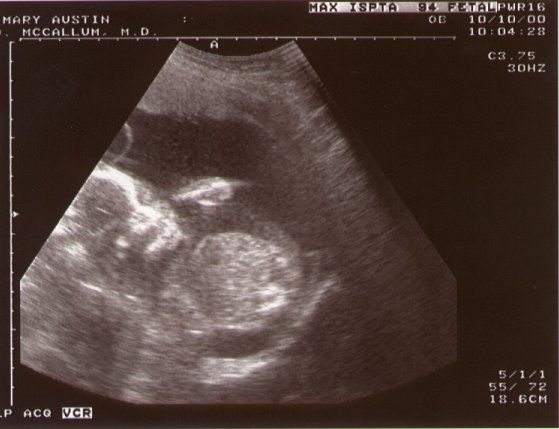

[10-oct]

this taken at 21 weeks.

The kids are transverse (laying sideways) and are head-to-toe.

[10-oct] This shot of baby A (aka "jordan")- she had her middle-finger up, to which MJ replied "that's george's daughter..."

[10-oct] And a nice shot of baby B (aka "taylor"), clearly showing torso, head and right arm- she was trying to suck her thumb!